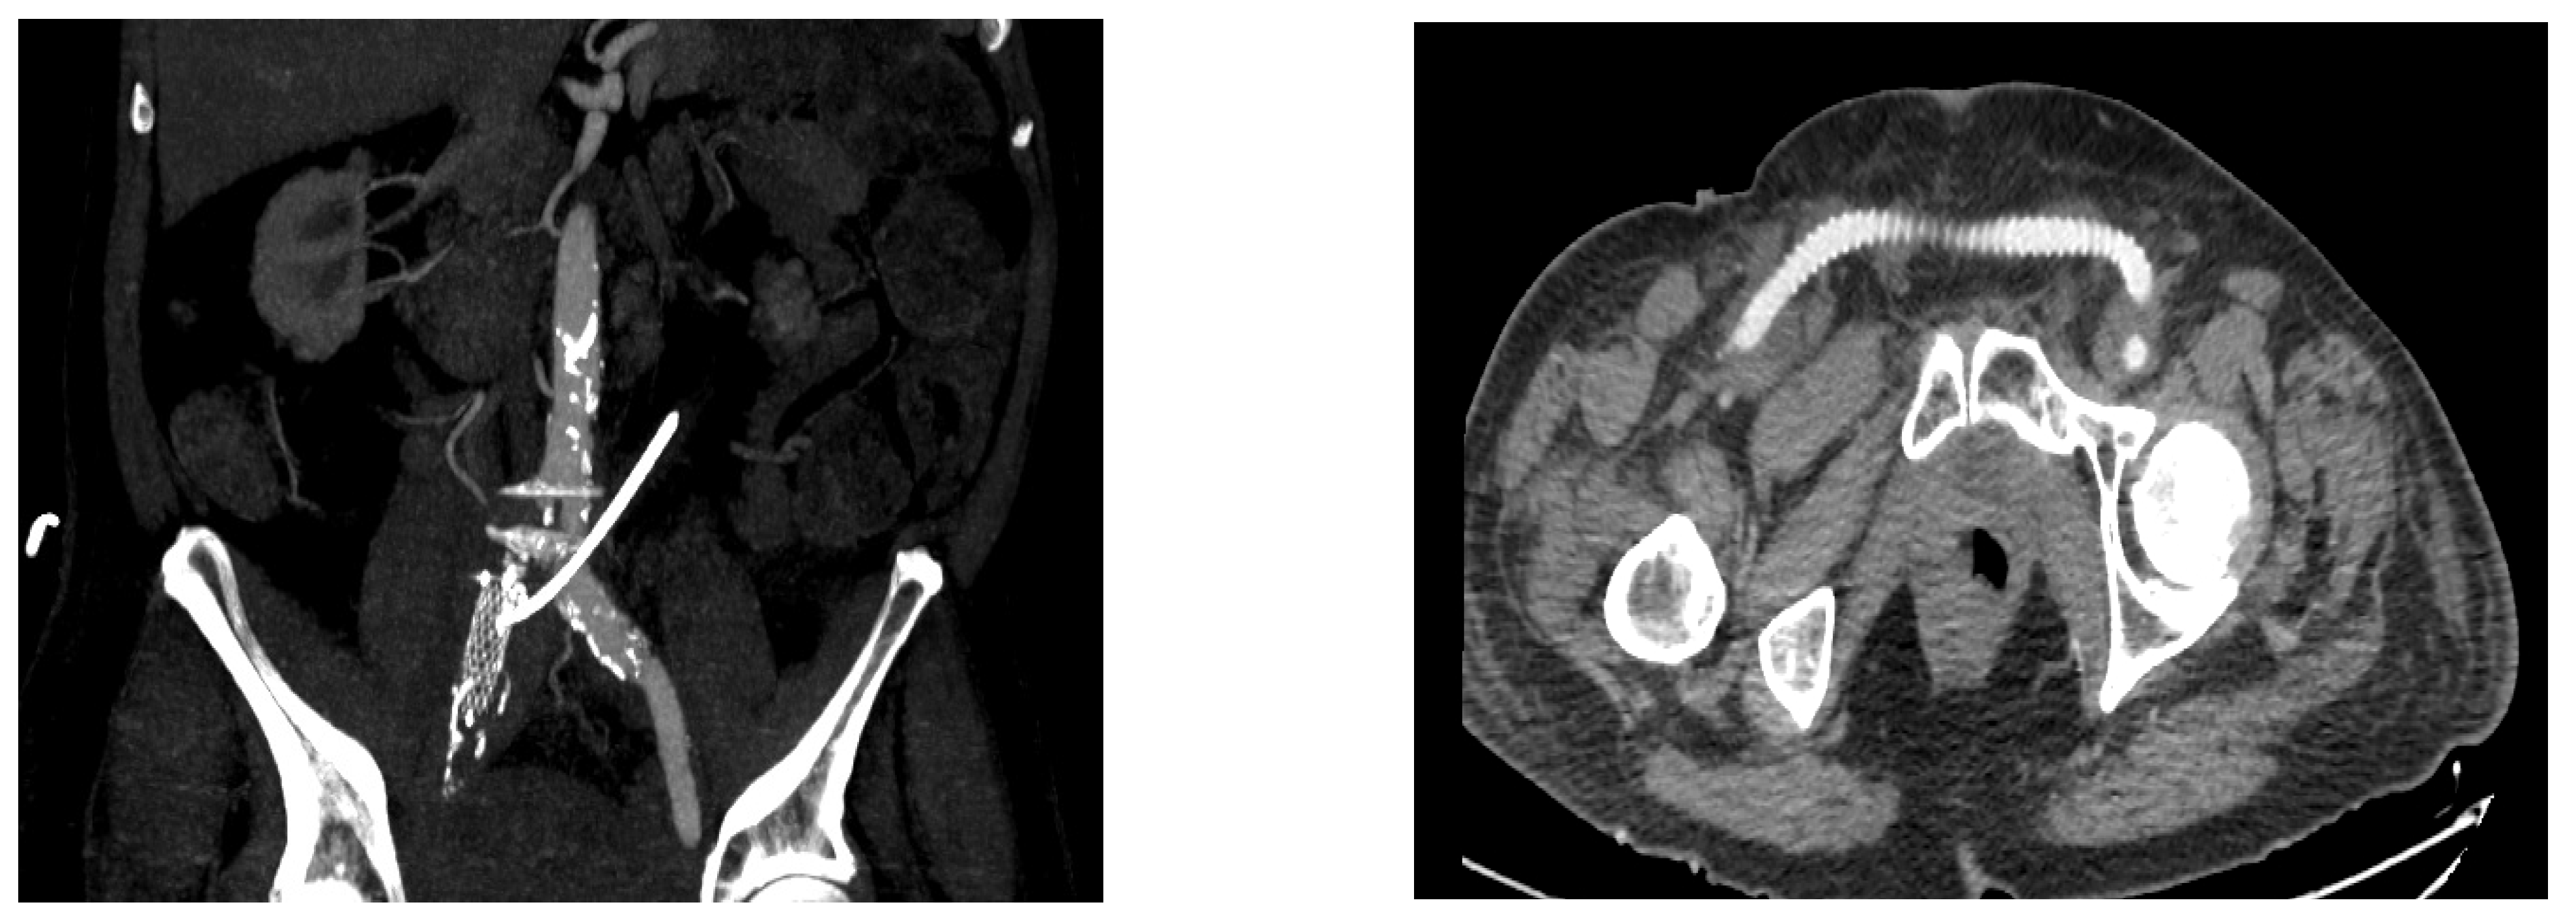

| CT scan | 5/9 (55.55) |

| Fistula location | |

| Left ureter–left CIA | 6/9 (66.66) |

| Left ureter–abdominal aorta | 1/9 (11.11) |

| Left ureter–EIA–descending colon | 1/9 (11.11) |

| Right ureter–right CIA | 1/9 (11.11) |

| 1 | 2012 | Negative | Positive | USC | Left ureter- left CIA | Endovascular stent | Nephrostomy | endovascular restenting | 7 | Dead | |

| 2 | 2013 | Negative | N/A | USC | Left ureter- Aorta | Aortic patch | Nephroureterectomy | 1 | Dead | ||

| 3 | 2015 | Positive | Positive | USC | Left ureter- left EIA+ colon | EIA ligation and FFC | ureter ligation +Nephrostomy | Left colectomy | 78 | Dead | |

| 4 | 2016 | Positive | Positive | USC | Left ureter- left CIA | CIA ligation and FFC | ureter ligation +Nephrostomy | 64 | Alive | ||

| 5 | 2018 | Positive | Negative | USC | Left ureter- left CIA | Endovascular stent | Nephrostomy | Nephrectomy | 32 | Alive | |

| 6 | 2019 | Negative | N/A | UPR | None | Left ureter- left CIA | Patch angioplasty | Nephroureterectomy | 27 | Alive | |

| 7 | 2020 | Positive | Negative | Bricker | Left ureter- left CIA | Endovascular stent | Nephrostomy | endovascular restenting | |||

| 2021 | Negative | Negative | Right ureter- right CIA | Endovascular stent | Nephrostomy | Ureter ligation +CIA ligation and FFC | 4 | Dead | |||

| 8 | 2021 | Negative | Positive | Bricker | Left ureter- left CIA | Endovascular stent | Nephrostomy | 10 | Alive | ||

| 9 | 2021 | Positive | Positive | USC | Left ureter- left CIA | Endovascular stent | Nephrostomy | 8 | Alive | ||